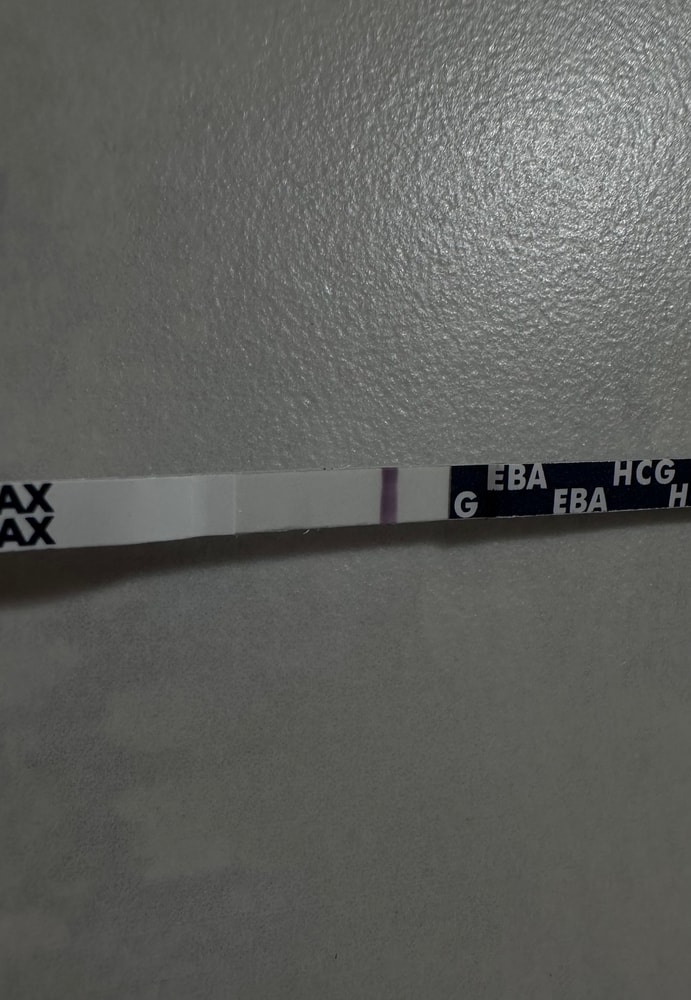

Писала сегодня пост с тенью на ЕВА

Писала сегодня пост с тенью на ЕВА

Тесты в студию🤗

Вот и мне отреагентили эти прекрасные тесты.